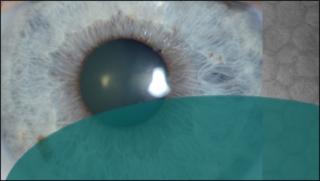

DMEK, from innovation to Classic

DMEK, from innovation (2006) to Classic (2024)